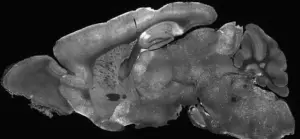

Researchers injected the modified adenoviruses into the cerebral ventricles of mice—the fluid-filled cavities in the brain—using a needle inserted past the eye.

This technique ensured the treatment reached the target areas of the brain.